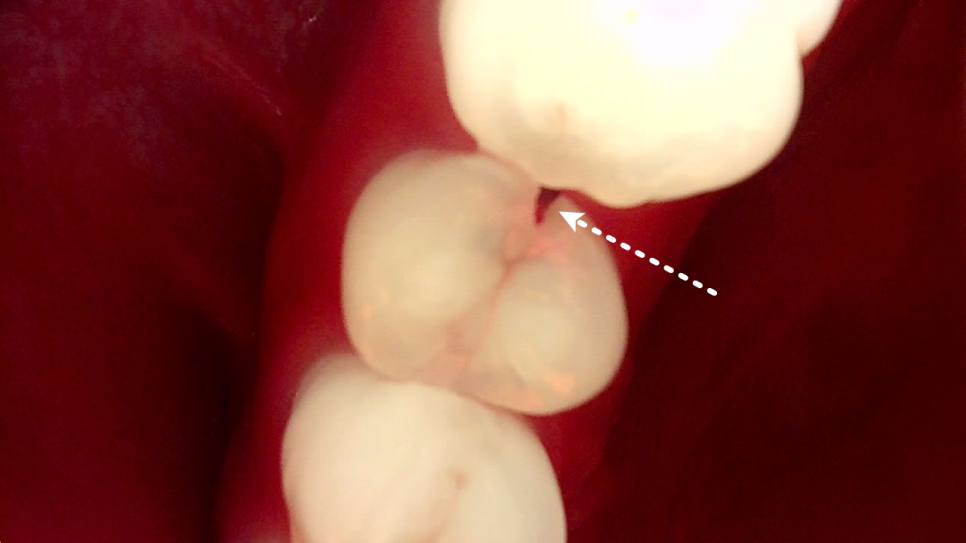

오늘의 환자분은 작은 어금니 안쪽 깊은 곳에 충치가 생긴 분이셨어요.

겉에서 보기엔 멀쩡해 보였지만, 큐레이 진단기로 확인해 보니 치아 속 깊이 숨어 있는 충치가 신경 바로 앞까지 도달해 있었죠.

큐레이는 눈에 잘 보이지 않는

충치와 균열을 보여주는

진단 장비인데요.

서초역치과

빛의 반사로 충치의 활성도를 색으로 표시하기 때문에 작은 구멍 속에서도 얼마나 진행됐는지를 한눈에 알 수 있어요.

깊은 충치로 인해 신경이 살짝 노출되어 있었어요.